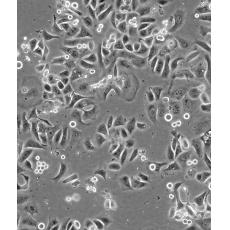

SK-BR-3 [SKBR-3;SKBR3]

產品名稱 SK-BR-3 [SKBR-3;SKBR3]

中文名稱 人乳腺腺癌細胞

生長特性 adherent

形態特征 epithelial